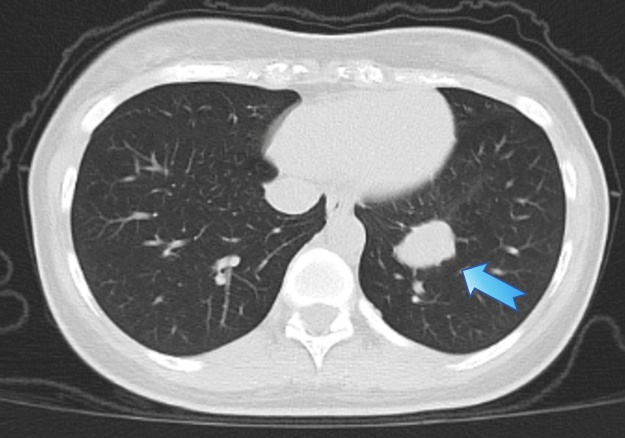

外院CT检查图像,箭头处为病灶

他们又赶往邻省另一家大医院,在接受抗感染治疗一周后,王女士又出现两次明显咯血。复诊复查CT显示:结节由约1.6 cm增至约2.7 cm。当地医生再次建议尽快手术,认为可能需切除较大范围的左肺叶。由于病灶血供丰富,穿刺风险很高,所以难以获取病理。随后几天,夫妻俩辗转4家医院,答复几乎一致:必须手术切除。